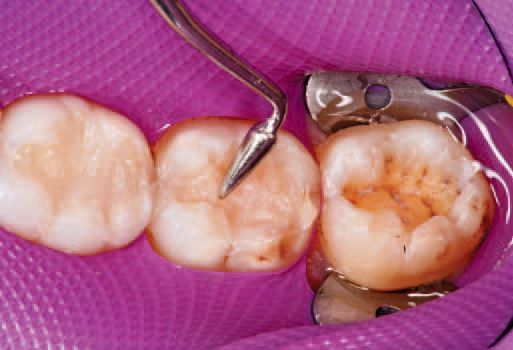

The ExciTE F adhesive was then light cured for 10 seconds. One increment of Tetric EvoCeram Bulk Fill shade IVA (for slightly reddish teeth) was then delivered to tooth No. 32 (Fig. 23).

An OptraSculpt sphere was then implemented to sculpt the composite to the floor and walls of the preparation (Fig. 24), after which an OptraSculpt pyramid was used to further form the tooth shape (Fig. 25).

The restoration, now fully formed, was light cured with the Bluephase Style for 10 seconds. Note that the shape of the light’s tip allowed easy access to the tight space. A fine, tree-shaped diamond, similar in shape to the P1 plugger, was then used to establish occlusal anatomy (Fig. 26).